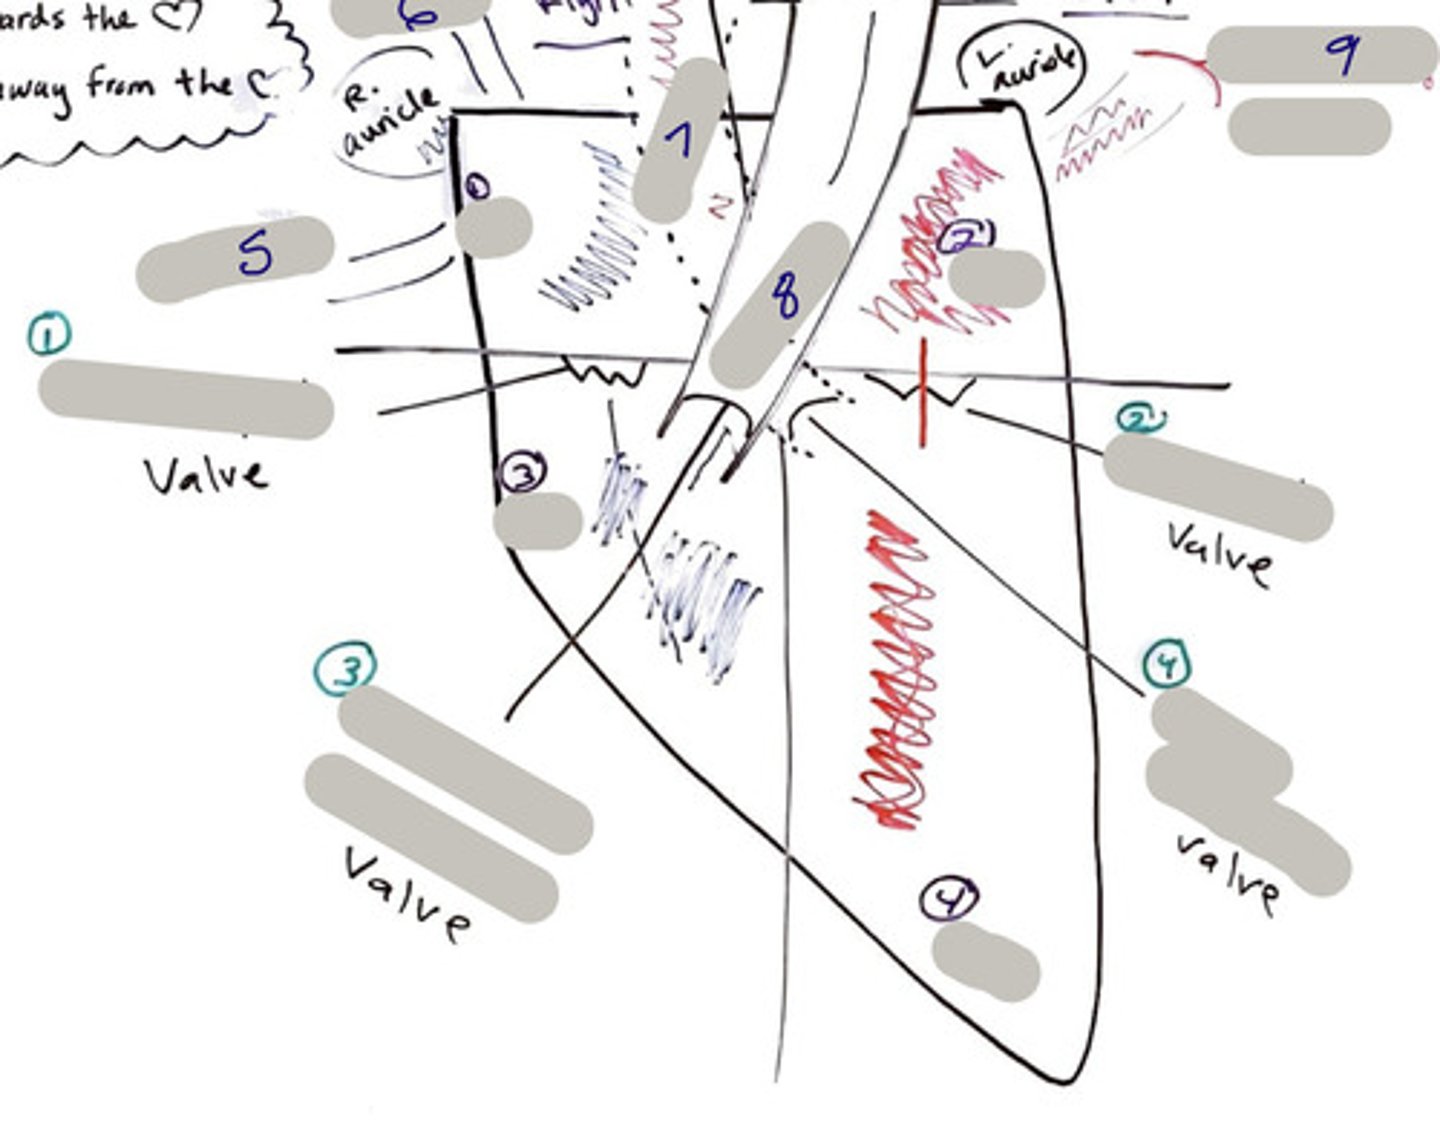

Tricuspid Valve (Right Atrioventricular Valve)

1-valve

Bicuspid valve (Left Atrioventricular Valve)

2-valve

Pulmonary Semilunar Valve

3-valve

Aortic Semilunar Valve

4-valve

Right Atrium

1-chamber

Left Atrium

2-chamber

Right Ventricle

3-chamber

Left Ventricle

4-chamber

Inferior Vena Cava

5-A vein that is the largest vein in the human body and returns blood to the right atrium of the heart from bodily parts below the diaphragm.

Superior Vena Cava

6-A vein that is the second largest vein in the human body and returns blood to the right atrium of the heart from the upper half of the body.

Aorta

7-The large arterial trunk that carries blood from the heart to be distributed by branch arteries through the body.

Pulmonary Trunk

8-carries blood from right ventricle to pulmonary arteries

Pulmonary veins

9-a vein carrying oxygenated blood from the lungs to the left atrium of the heart.